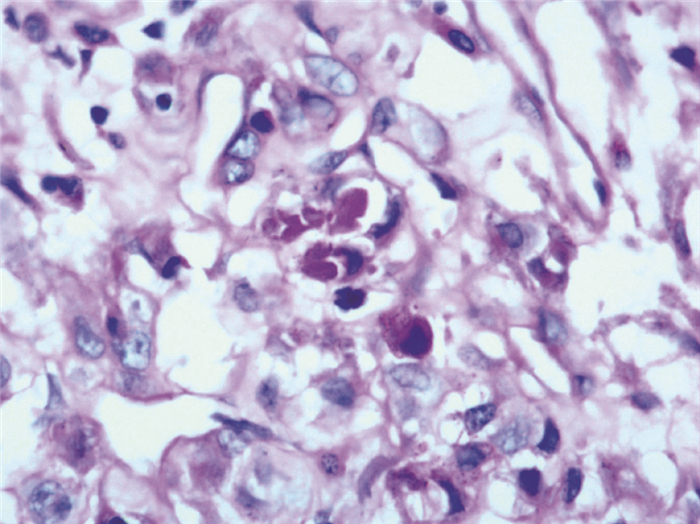

显微镜观察:低倍镜下,瘤组织呈实性弥漫片状生长并且被纤维组织分隔,未见明显的“腺泡状”或“器官样”的细胞巢,局部被纤维分隔呈结节状(图 2A),细胞巢之间有宽窄不等的血窦间隔(图 2B),可见血管内瘤栓(图 2C)。高倍镜下细胞边界清晰,大小和形状较为一致,呈多边形或者大圆形,胞质丰富,细胞核呈泡状,有明显的核仁,细胞核大小不齐,细胞浆呈嗜伊红颗粒状(图 2D)。

图 2 一例ASPS患者肿块组织病理切片的显微镜下所见(HE染色,A×40、B、C×100,D×200) A:瘤组织呈实性生长并且被纤维组织分隔,局部被分隔呈结节状;B:细胞巢之间有宽窄不等的血窦间隔;C:可见血管内瘤栓;D:高倍镜下细胞边界清晰,细胞核呈泡状,有明显的核仁,细胞核大小不齐,细胞浆呈嗜伊红颗粒状